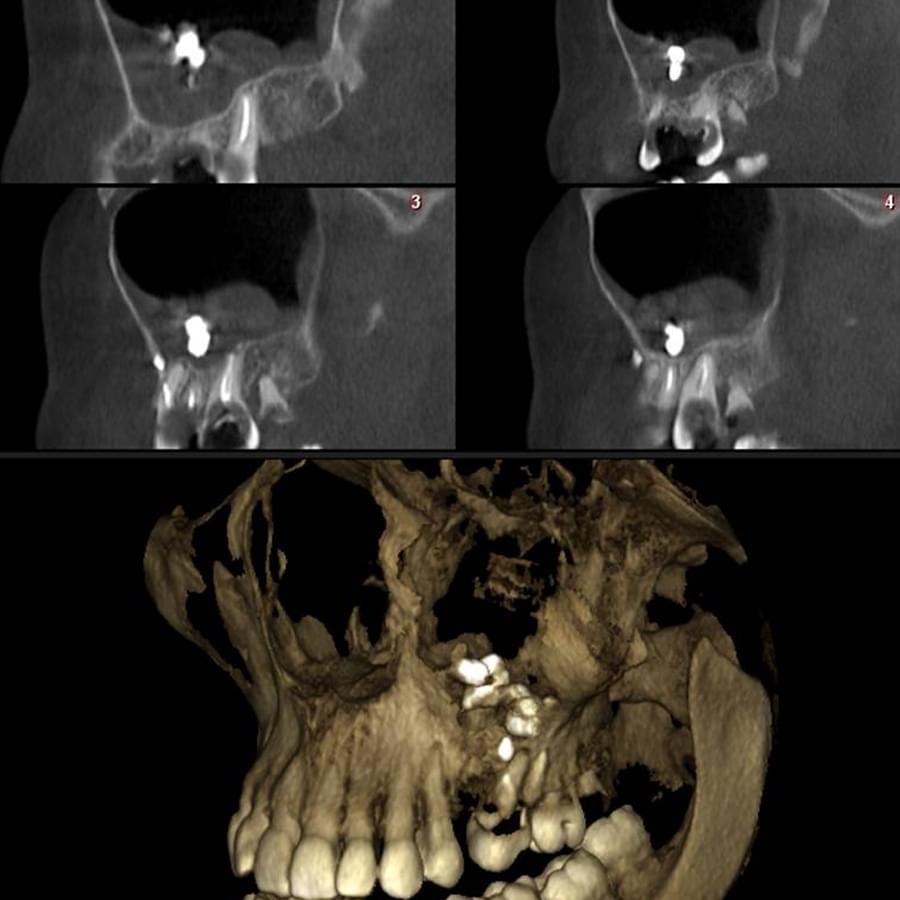

Комп'ютерна томографія

Щелепно-лицева діагностика

3D цефалометричний аналіз є сучасною технологією, яка дозволяє отримувати точніші,

комплексніші та надійніші дані про зубну та скелетну структуру. Ця технологія може стати

великим кроком в перед для ортодонтів, які хочуть забезпечити найкраще можливе лікування

своїх пацієнтів.

Основні переваги 3D цефалометричного аналізу:

Точність: 3D цефалометричний аналіз забезпечує точніше визначення розмірів та відстаней між

зубами та кістковими структурами.

Комплексність: ця технологія дозволяє отримувати детальні дані про різні структури, такі як

кістка та м'язи, що дозволяє ортодонтам докладніше досліджувати деякі патології та планувати

лікування.

Надійність: 3D цефалометричний аналіз дозволяє отримувати надійніші результати, оскільки

виключає можливість помилок, пов'язаних зі спотворенням або перекриттям зображень.